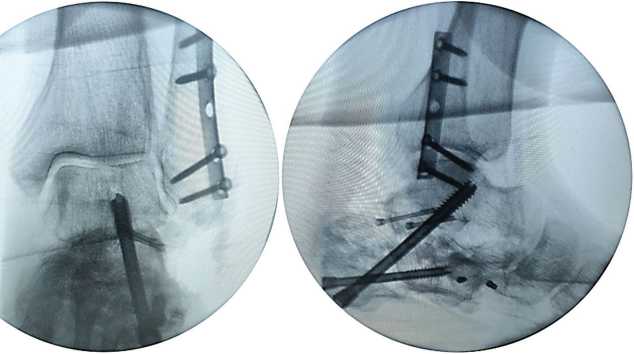

Рис. 5. Рентгенограммы левой стопы в прямой и боковой проекциях под нагрузкой весом тела

Для уточнения хода линий перелома, взаиморасположения и степени консолидации фрагментов пяточной кости пациенту выполнена МСКТ левой пяточной кости, в ходе которой подтвержден исходный суставно-депрессионный характер перелома, выраженный пяточно-малоберцовый конфликт, а также уточнены форма и взаиморасположение консолидированных фрагментов пяточной кости и металлоконструкций (рис. 6).

Рис. 6. МСКТ левой стопы в коронарной, саггитальной и аксиальной плоскостях [16]